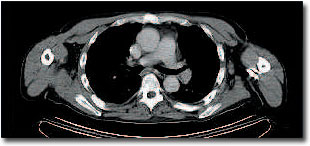

CT

Bei einem Patienten mit Non-Hodgkin- Lymphom (Lymphknotenkrebs) wurde nach der Chemotherapie eine PET/CT durchgeführt. In der Achsel wird in der PET eine Lymphknotenmetastase sichtbar, die in der CT allein nicht zu erkennen ist. Anhand der PET/CT-Kombinationsaufnahme lässt sich die Metastase exakt lokalisieren. |